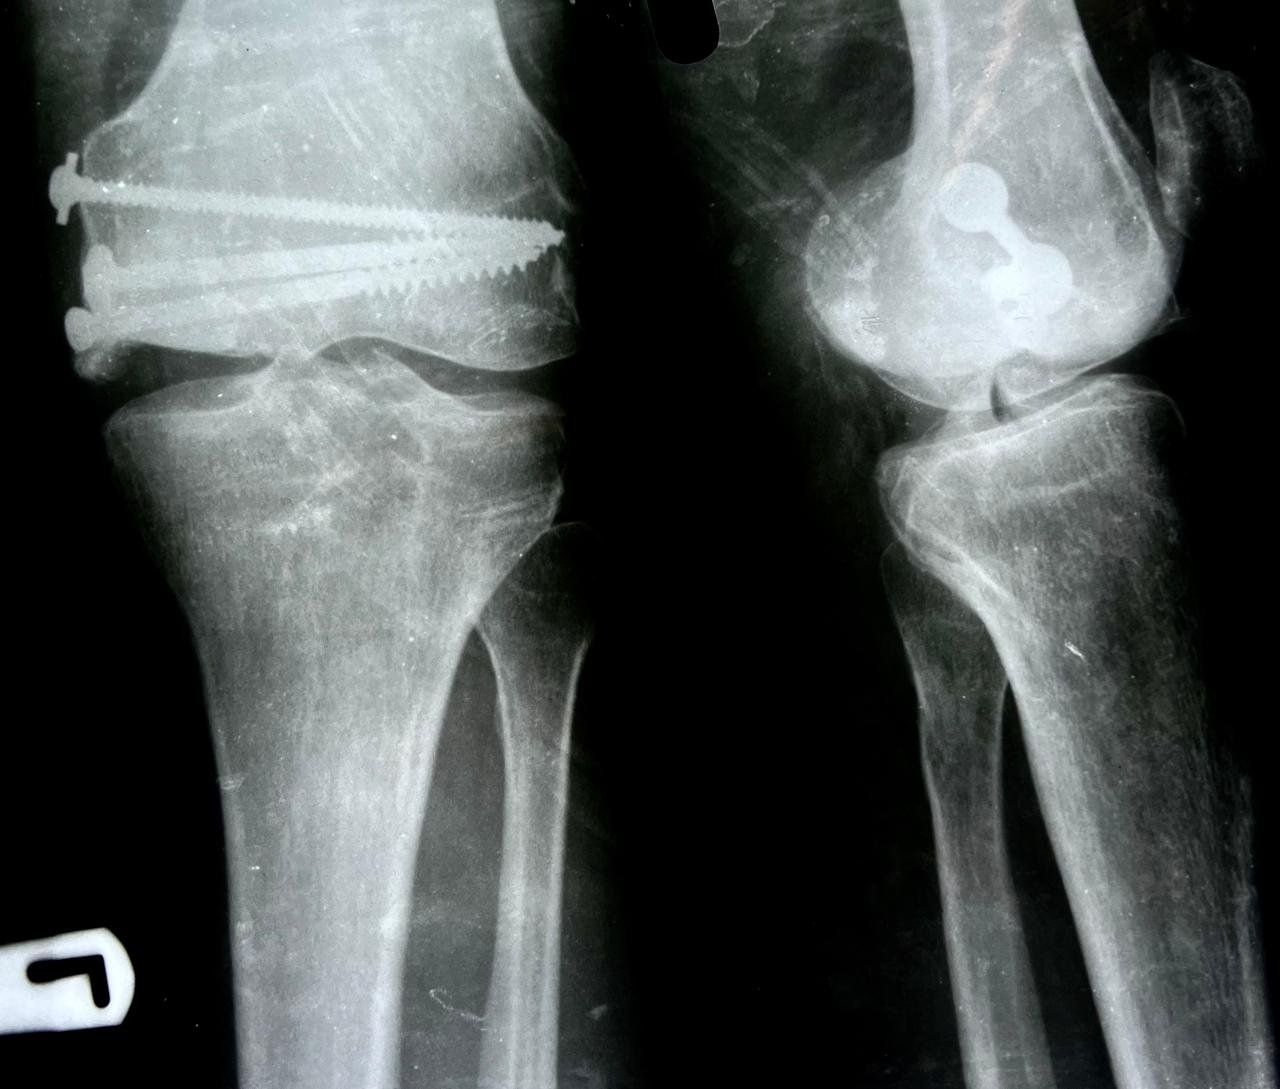

Pre op & postop X-ray compound fracture lower tibia

& fibula | Heal fracture pre & postop | Clavicle